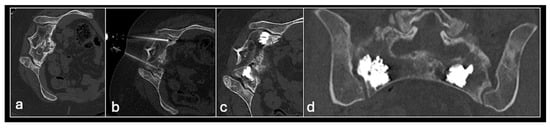

Figure 13. Axial CT (a) showing metastasis in the sacrum. Images (bd) showing sacroplasty with cement in both sacral ala.

3.5.2. Cement Augmentation

Cement augmentation is the injection of polymethylmethacrylate cement (PMMA) mixture into a bony defect to restore bony structural integrity and provide pain relief. The most common form is vertebroplasty in the context of vertebral compression fractures which—in the setting of oncology—include pathological fractures with underlying myeloma or metastases with resultant pain and disability refractory to conservative treatment. The procedure is also a useful adjunct following percutaneous ablation to restore structural integrity following bone destruction, particularly for larger lesions [33] (Figure 13 and Figure 14).

The most common type of cement augmentation at our centre is vertebroplasty. This is typically performed via a transpedicular approach into the lesion using an 11 G or 14 G bone biopsy needle system. Biopsy samples may be taken with the PMMA and then injected into the defect. A modified procedure is the kyphoplasty in which cement injection is preceded by the inflation of a balloon device in the vertebral body to create space with the cavity then filled with the cement. This is more effective in pain relief and minimises leakage but results in a longer and more expensive procedure [4,63].

Other variants with similar underlying principles include sacroplasty and acetabuloplasty. Complications to be aware of include cement leakage, which can lead to cement thrombosis, pulmonary emboli and compression of adjacent structures [64,65]. Nevertheless, cement augmentation generally remains a relatively safe and effective minimally invasive procedure, which can greatly improve patient quality of life in a palliative setting.